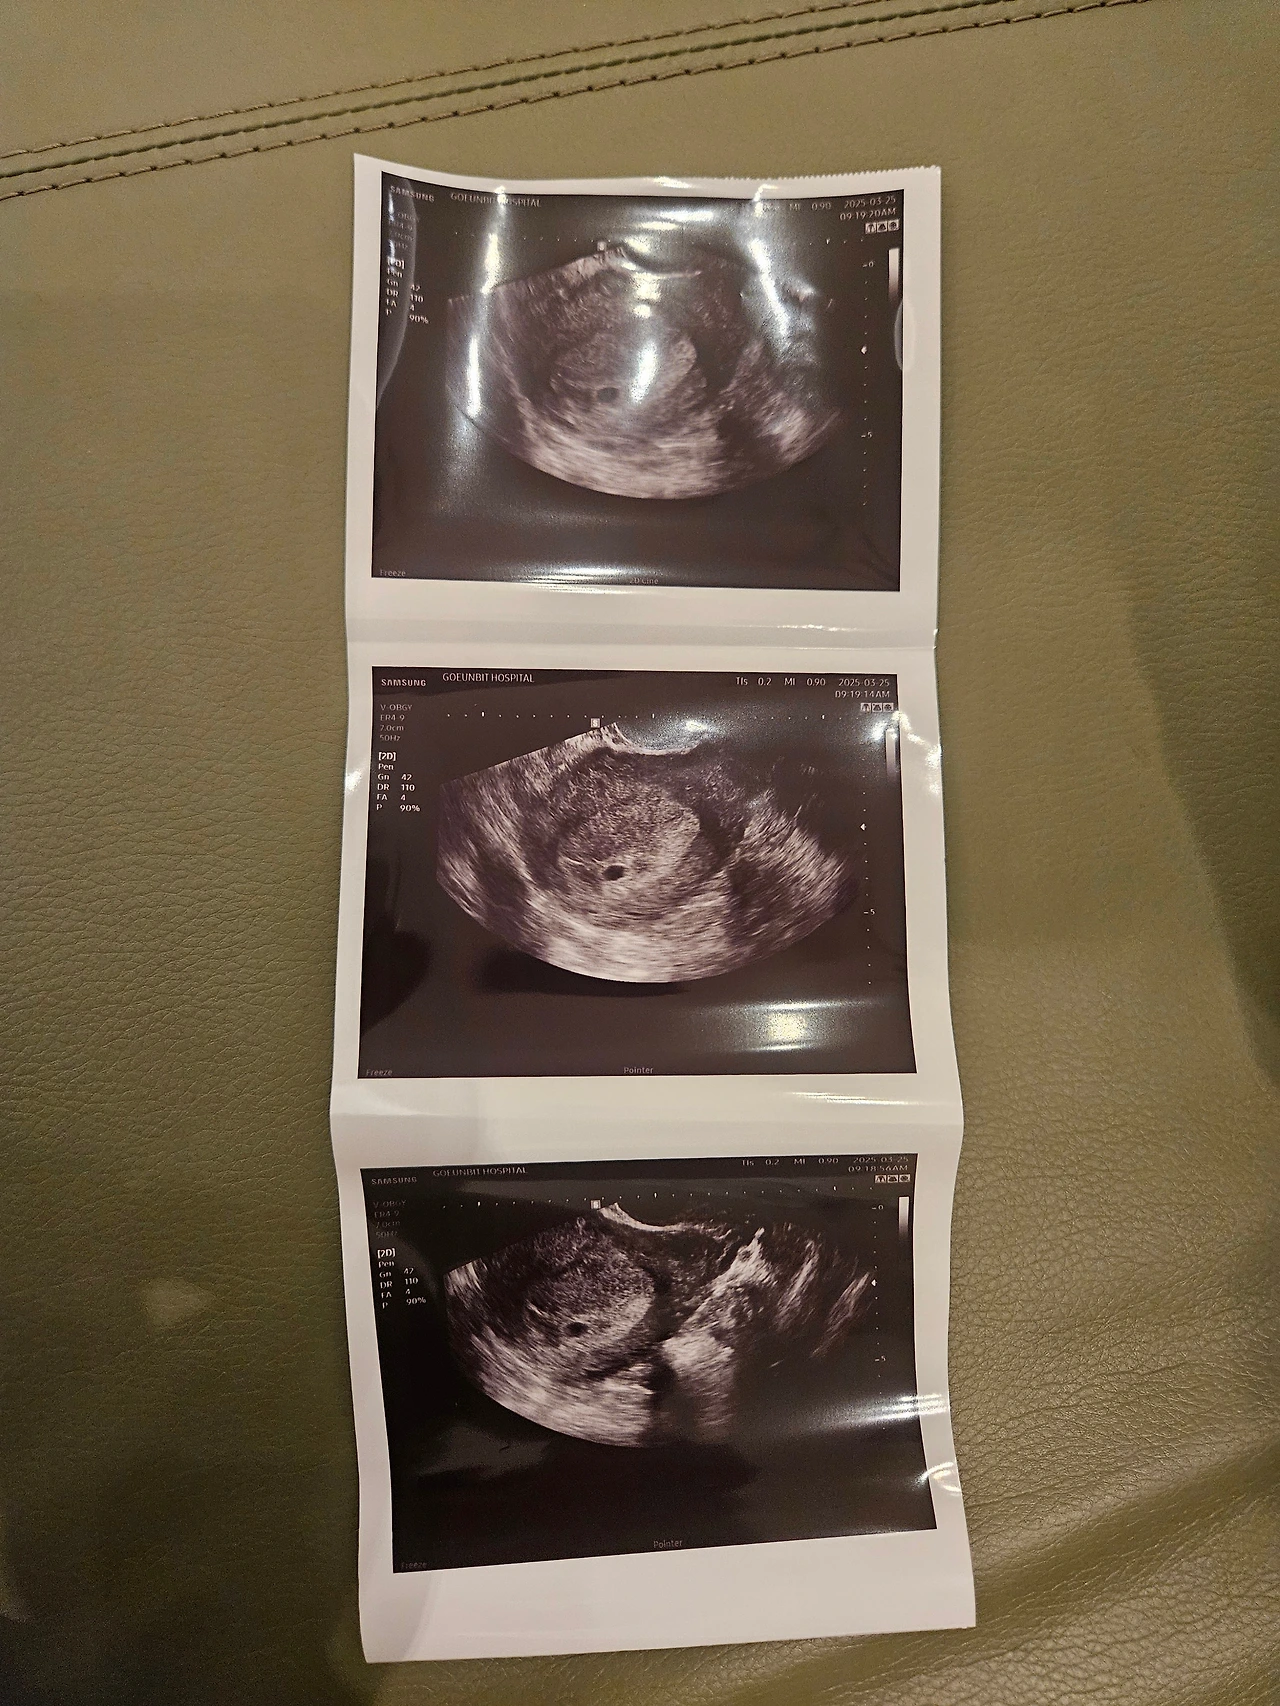

넌 두줄로 네 존재감을 뽐낸 후 아무 소식이 없었지. 속이 메슥거리지도 않고, 먹고 싶은 것도 없었어. 심지어 졸리지도 않아서 꼬물이 얘는 엄청 순해서 엄마를 도와주는 줄로만 알았어. 5주 차에 병원에 갔을 때도 아기집과 난황이 조그마하게 있어서 잘 자라고만 있는 줄 알았어.

7주가 되어 병원에 갔지. 2시간을 기다려서 만난 화면 속의 너는 더 커진 아기집에 없었어. 원래대로라면 200에 근접한 심장소리가 들려야 하는데 텅 빈 화면을 보니 멍하더라. 선생님은 초기의 유산은 유전자의 문제라 부모 잘못이 아니라고 하셨지만. 그냥 눈물이 나오더라. 아빠랑 싸웠어도 내가 먼저 풀고 화해하며 스트레스를 줄일걸. 좀 더 자고 잘 먹을걸 후회만 되고 미안하더라고.

미안해. 이제 수술로 아기집도 없어졌고 여전히 식욕도 없고 생각나는 게 없어. 욕심 없는 꼬물이. 초음파 사진 한 장만 남아서 너를 기억하는 게 너무 없어서 아쉽다.